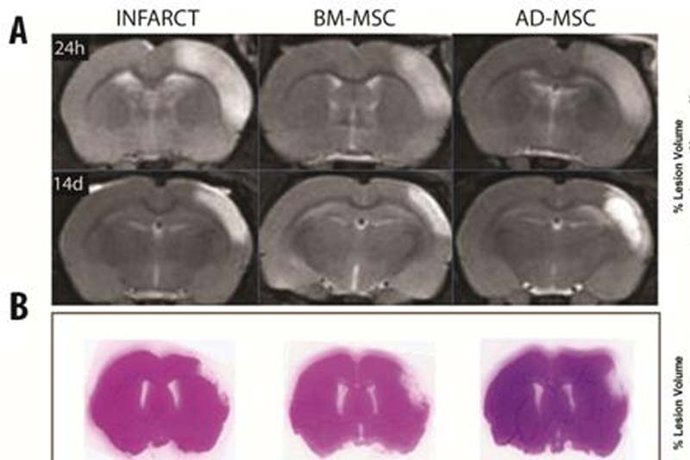

Las células madre de médula ósea o tejido adiposo ayudan a la recuperación tras un ictus isquémico en un modelo animal, según investigadores españoles, quienes han realizado un estudio, que ha sido publicado en 'Stem Cell Researh & Therapy de Biomed Central'.

En concreto, investigadores del Servicio de Neurología del Hospital La Paz y del grupo de Neurología y Enfermedades Cerebrovasculares del Área de Neurociencias del IdiPAZ, dirigido por el doctor Exuperio Díez-Tejedor, han observado cómo el tratamiento con estas células mejoró la reparación del cerebro y la capacidad de los animales para completar tareas de comportamiento.

Para el estudio, se analizaron dos grupos de ratas que sufrieron un accidente cerebrovascular. Al primero se le trató, 30 minutos después, con células madre administradas por vía intravenosa y, al segundo, con una solución salina.

Pasadas 24 horas del tratamiento, las ratas tratadas mostraron una mejor recuperación funcional que las del grupo control y, dos semanas después, estaban cerca de los niveles normales en las pruebas funcionales.

Esta mejora se observó a pesar de que las células no parece que migren a la zona dañada del cerebro. Las ratas tratadas también tenían mayores niveles de marcadores biológicos implicados en la reparación y plasticidad cerebral.

El resultado positivo en la reparación cerebral de los roedores se observó tanto en los casos en el que se utilizaron células de tejido adiposo cómo en los de médula ósea.

Según Díez-Tejedor, la mejora en la recuperación "se observó independientemente del origen de las células madre, lo que puede ampliar la aplicabilidad del tratamiento en ensayos con humanos, en donde las células derivadas de tejido adiposo, en particular, son abundantes y fáciles de obtener sin cirugía invasiva".